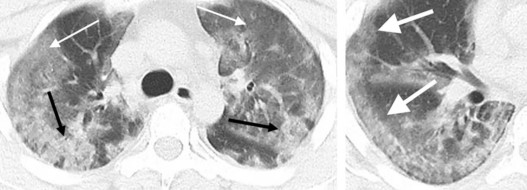

Epidémie de Covid-19 : Point sur l'imagerie

La France est actuellement en situation épidémique de stade 2 vis-à-vis du SARS-Cov-2, et la sollicitation des structures radiologiques, qu'elles soient hospitalières ou non, devient plus importante.

Cette montée en charge nécessite de clarifier le rôle de l'imagerie dans ce contexte épidémique :

Imagerie COVID » COVID-19 : Rôle du radiologue Pr Antoine Khalil »